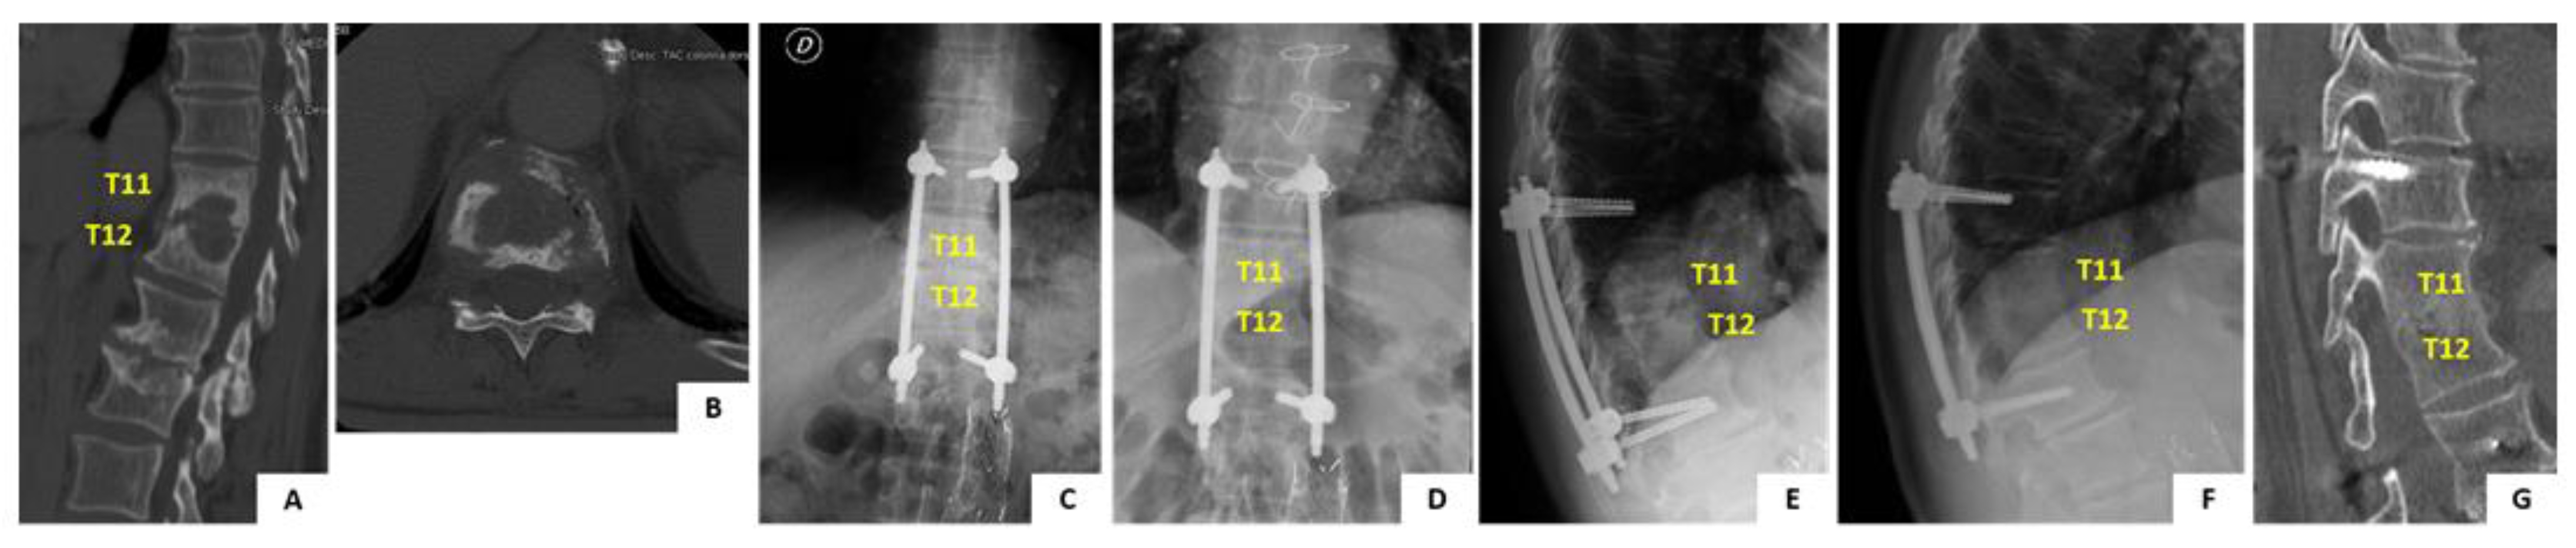

In June 2009, a 68-year old man presented to you hospital with a 1 month history of worsening axial back pain at the thoracolumbar junction. Past medical history of the patient was positive for high blood pressure and benign prostatic hyperplasia. At first the patient was assessed by his general practictioner and was prescribed oral antibiotic therapy with ciprofloxacin for a suspect urinary tract infection. Therapy was unsuccessful and patient developed fever, night sweats and fatigue over the course of the following 15 days. The patient was admitted to our hospital with the suspect diagnosis of pyogenic spondylodiscitis. Spinal X-ray, CT and MRI scans were obtained (Figure 5A,B). Imaging showed destructive lesion at T11-T12 with disc and endplate involvement, suggestive of pyogenic spondylodiscitis type B3.1 [11]. A CT guided biopsy of the lesion was positive for S. hominis pyogenic infection. The patient was started on intravenous teicoplanin and ceftriaxone therapy which was continued for 4 weeks and followed by other 4 weeks of iv therapy with teicoplanin and co-trimoxazole. At the end of iv antibiotic therapy the patient was prescribed oral therapy with co-trimoxazole and rifampicin for 4 more weeks. Before starting antibiotic therapy the patient was prescribed a rigid TLSO brace to relieve pain and prevent development of spinal deformity. The brace was poorly tolerated by the patient and for this reason operative treatment with percutaneous posterior screw-rod instrumentation was offered. Posterior fixation from T10 to L1 was performed uneventfully (Figure 5C,E). The patient was allowed free mobilization soon after surgery. Clinical and laboratory parameters improved significantly over the course of the follow-up and complete healing of the infection was determined at 3 months after the diagnosis. The patient is currently 80-years old and completed the 10-years follow-up after the procedure. He lives indepedently at home, does not complain of any back pain. The imaging obtained at 10 years follow-up shows complete healing of the lesion with fusion of the vertebral bodies. No mobilization of the instrumentation is noted (Figure 5D,F).

Figure 5.

Pre- and post-operative imaging of the case report detailed in the manuscript. Panels (A,B) show sagittal and axial CT scan imaging of the T11–T12 infected level. Panels (C,D) show comparison of standing AP X-ray imaging of the spine immediately after surgery and at 10 years follow-up. Instrumentation is noted with pedicle screws and rods. The instrumentation is bridging the infected level. Panels (E–G) show comparison of standing lateral view X-ray imaging of the spine immediately after surgery and at 10 years follow-up. No mobilization of the instrumentarion is noted, the infected level is completely fused and segmental kyphosis is preserved.